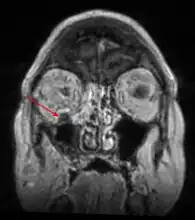

Imaging

Imaging is often performed, such as CT scan of lungs and sinuses.[38] Signs on chest CT scans, such as nodules, cavities, halo signs, pleural effusion and wedge-shaped shadows, showing invasion of blood vessels may suggest a fungal infection, but does not confirm mucormycosis.[16] A reverse halo sign in a person with a blood cancer and low neutrophil count, is highly suggestive of mucormycosis.[16] CT scan images of mucormycosis can be useful to distinguish mucormycosis of the orbit and cellulitis of the orbit, but imaging may look identical to those of aspergillosis.[16] MRI may also be useful.[39]

MRI head: right sided sinus involvement extending into the orbit. -